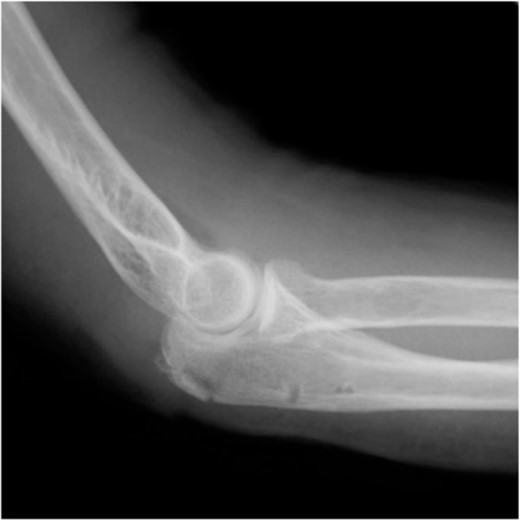

A 65-year-old healthy Japanese woman fell on her hands with her right elbow extended. She presented to our hospital with pain and swelling in the right elbow joint; active extension was impossible. X-rays showed a triceps tendon avulsion fracture (Fig. 1). Her bone mineral density, using dual X-ray absorptiometry, was 71% of the young adult mean for the lumbar spine. She was diagnosed with an avulsion fracture of the right olecranon (AO classification: 2U1A1) and underwent surgery 7 days post-injury.

Plain radiographs of the right elbow show no abnormal findings in the anteroposterior view (A); however, an avulsion fracture of the olecranon is observed in the lateral view (B).